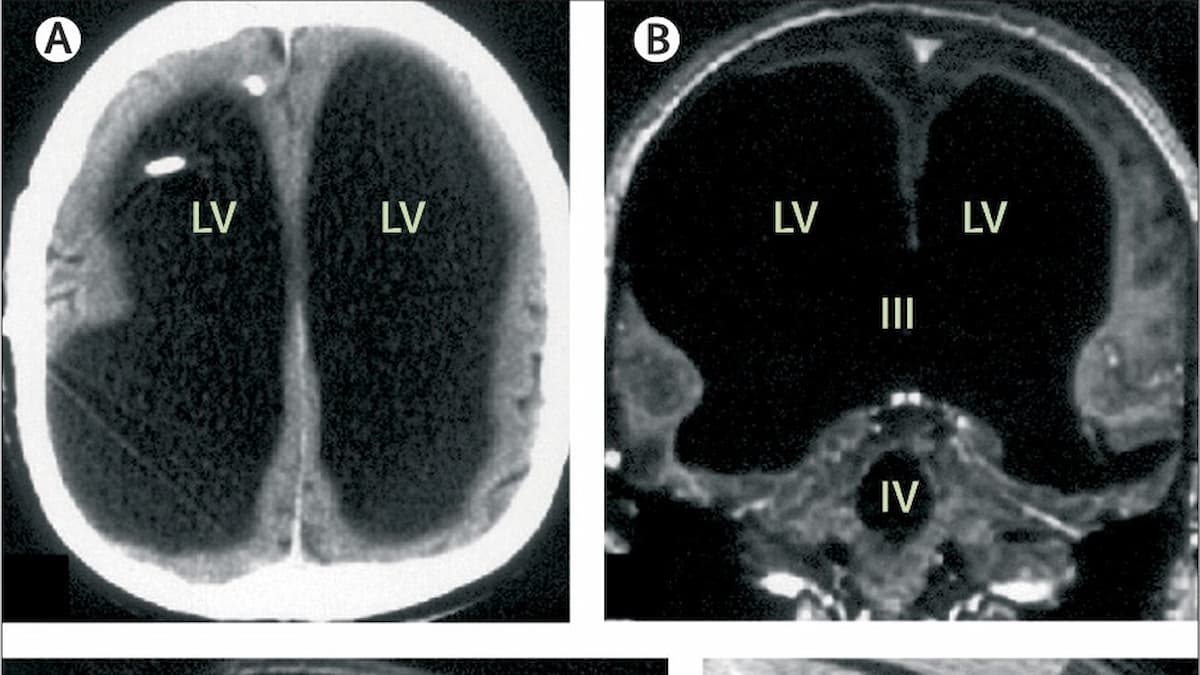

The puzzling medical case was first published in The Lancet medical journal in 2007 but it still baffles people to this day. The man had been experiencing a weakness in one of his legs which is what prompted him to speak to doctors in the first place. According to CBC.ca, while testing the man, doctors discovered that instead of having a brain inside his skull, the 44-year-old man’s head was full of liquid with just a thin layer of brain tissue in his skull. The condition is known as hydrocephalus.

Hydrocephalus affects 1 in 1,000 people according to an article from nature.com, it is usually treated with shunts that drain the fluid. In most cases those affected can live normal lives although there can be neurological issues. The French man’s case is an extreme example of the condition and yet it didn’t adversely affect his neurological development.